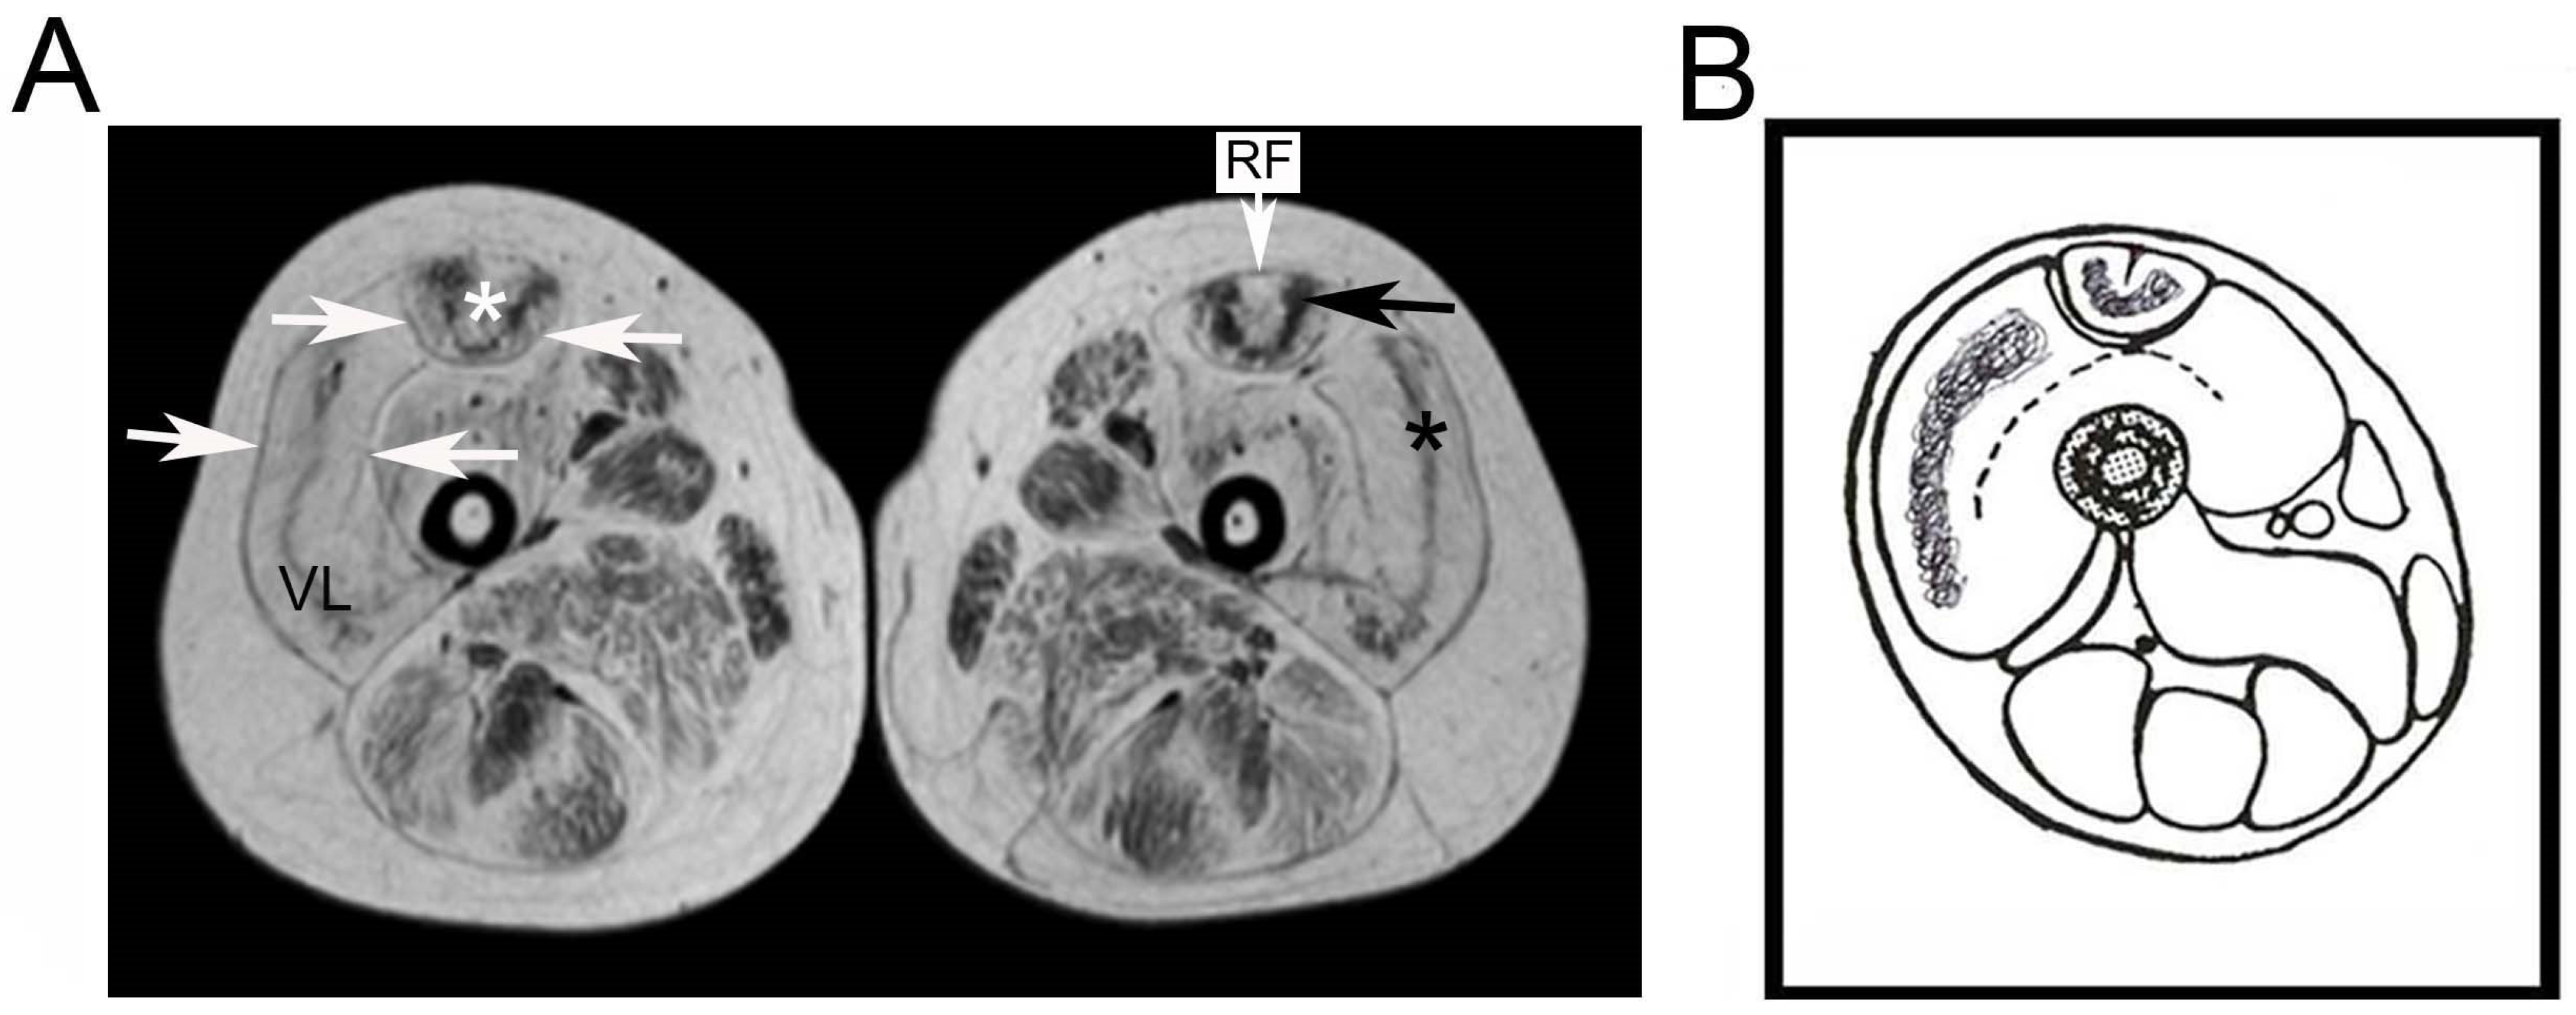

Early Morphological Changes of the Rectus Femoris Muscle and Deep Fascia in Ullrich Congenital Muscular Dystrophy

- Mercuri, E.; Lampe, A.; Allsop, J.; Knight, R.; Pane, M.; Kinali, M.; Bonnemann, C.; Flanigan, K.; Lapini, I.; Bushby, K.; et al. Muscle MRI in Ullrich congenital muscular dystrophy and Bethlem myopathy. Neuromuscul. Disord. 2005, 15. [Google Scholar] [CrossRef] [PubMed]